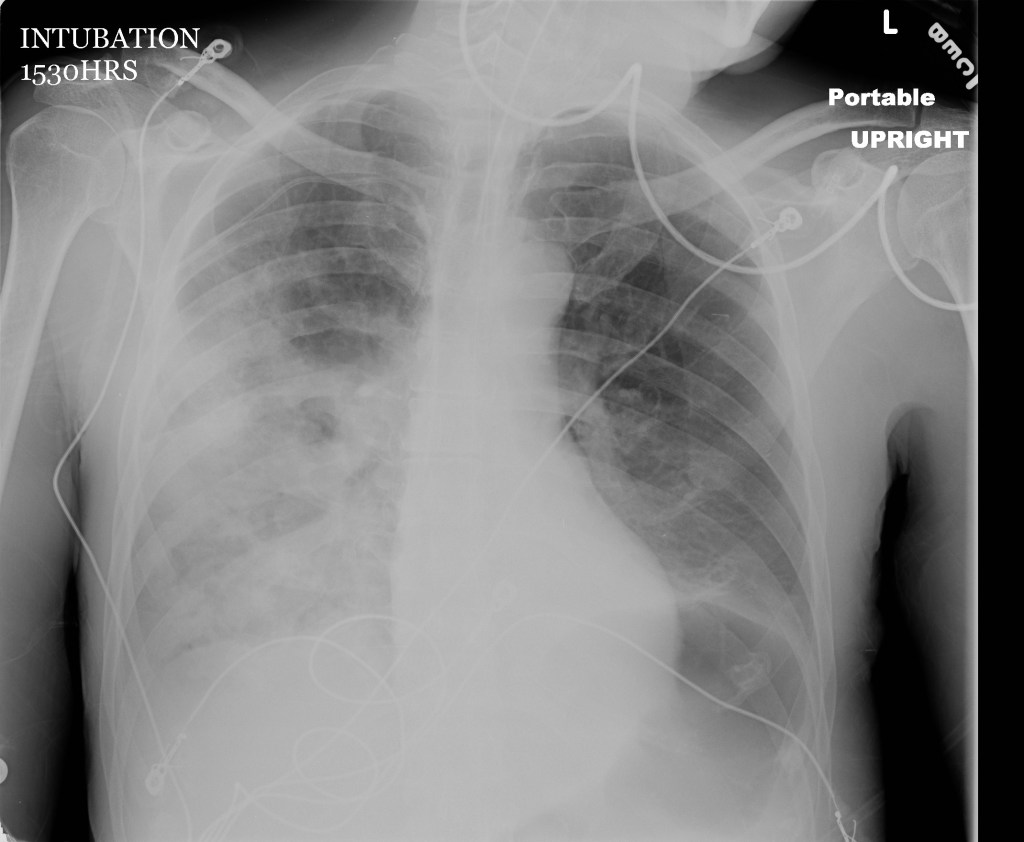

This case is important because it highlights a rare cause of cardiac arrest where the patient presents with several risk factors that could be identified as the clues to the obstructive respiratory pathology. It also highlights the need to move to an advanced airway when BVM is ineffective during cardiac arrest. Lastly, it’s also is an opportunity to practice troubleshooting a FB in the airway which can be really stressful.

This case involves a 60-year-old male patient who arrives VSA in PEA after collapsing while eating dinner with family. The collateral history included that he was suspected to be intoxicated. The patient is difficult to bag with EMS. The learner will have to work through the can’t ventilate/can’t oxygenate scenario once they identify that BVM is ineffective.

Image courtesy of http://maryland.ccproject.com/wp-content/uploads/sites/3/2013/09/Necrotizing-Pneumonia.jpg